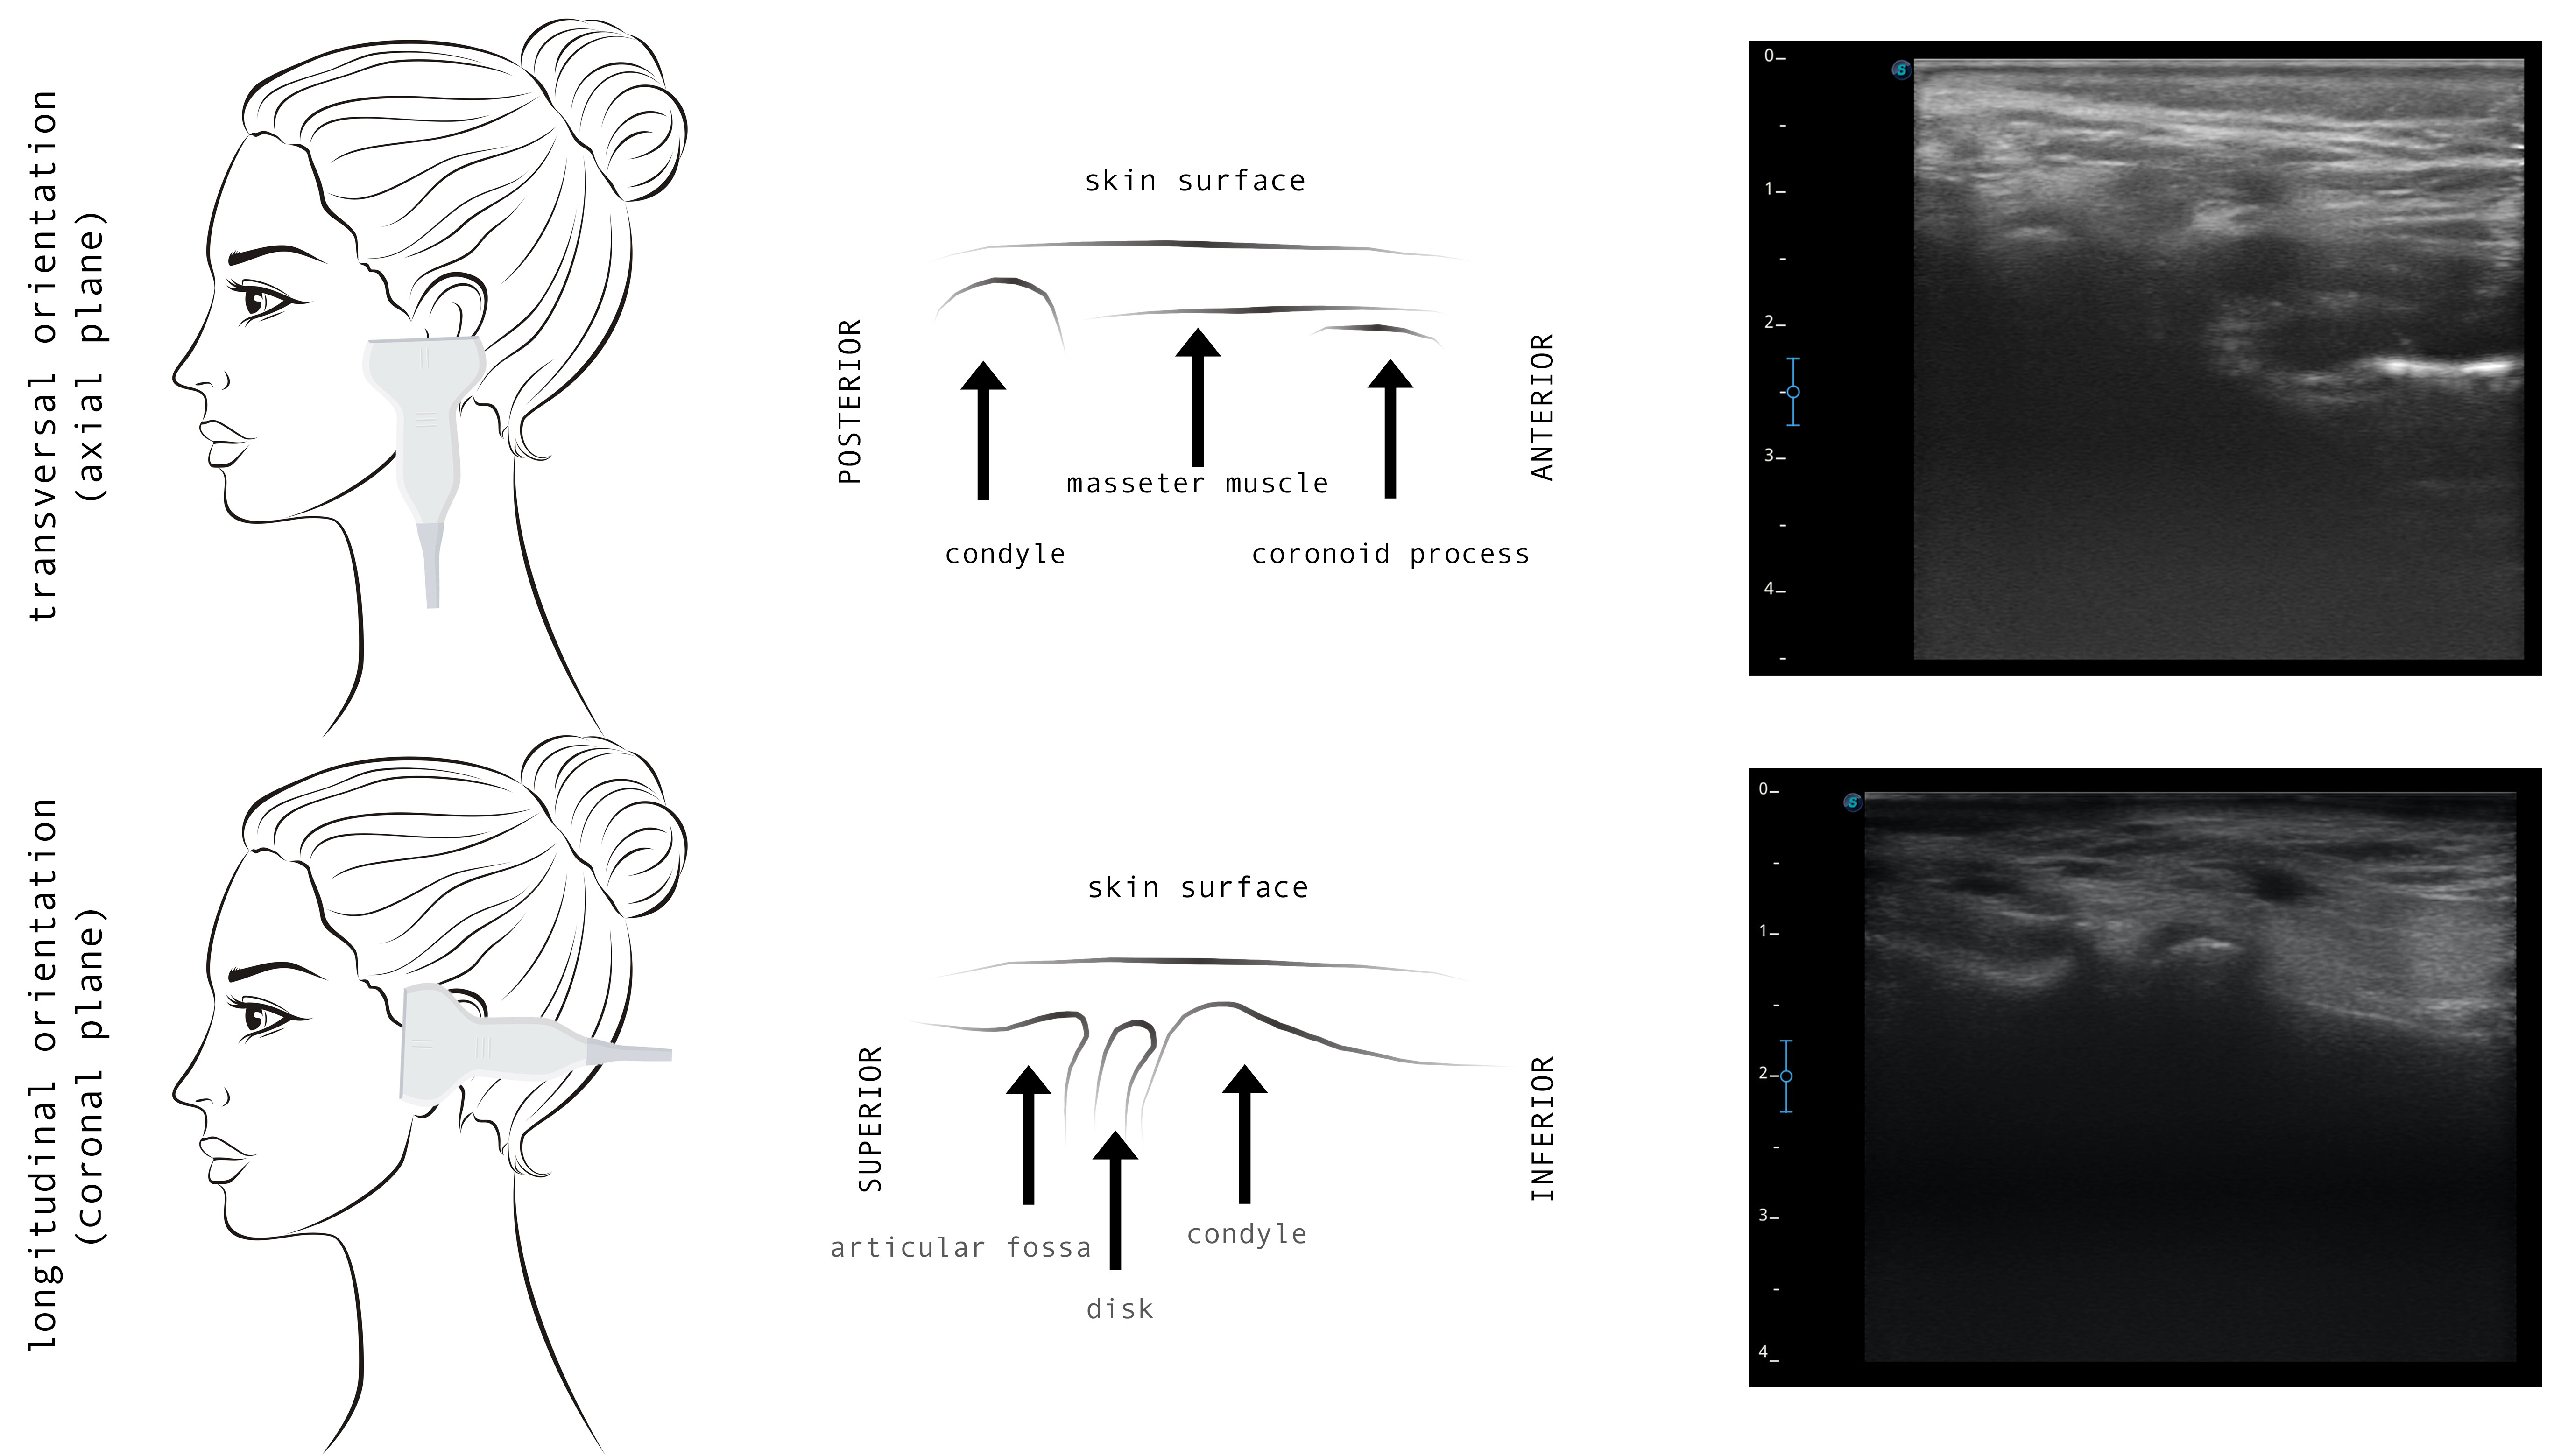

In most publications, TMJ US monitoring is based on the standardized protocol of Emshoff et al.43 Most studies have adopted similar protocols, which include transversal and longitudinal scans to evaluate the joint compartments in the coronal, axial and oblique planes (Figure 2).41 During the longitudinal scanning, the probe is placed over TMJ, perpendicular to the zygomatic arch and parallel to the mandibular ramus, and inclined until the best view is achieved; then static and dynamic evaluations are performed (Figure 3).38 The performance of the US diagnostics is outside the scope of the present review and has been extensively described for 3 main diagnostic domains: disk displacement; joint effusion; and cortical erosion.38, 40, 41, 42, 44 It has been suggested that US can complement a clinical examination as an initial evaluation tool.40